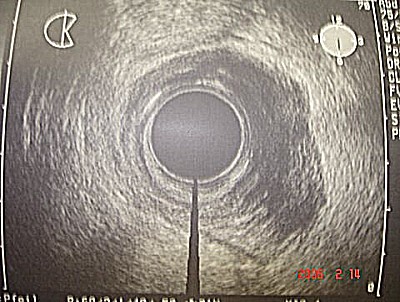

Abb. 7: Bösartiger Tumor des unteren Mastdarmes T3, der die eigentliche Mastdarmmuskulatur soeben erreicht hat. Abb. 7: Bösartiger Tumor des unteren Mastdarmes T3, der die eigentliche Mastdarmmuskulatur soeben erreicht hat.